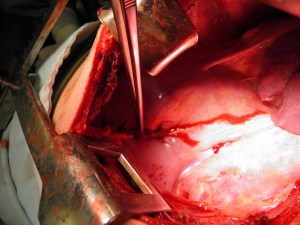

Hydatid cyst

Hydatid cyst (photo provided by Dr. Firas Abu Akar)